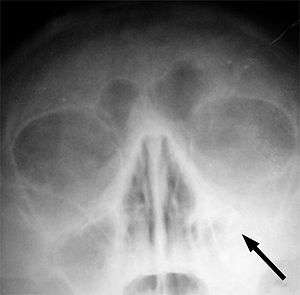

Left-sided maxillary sinusitis marked by an arrow. Note the lack of the air transparency indicating fluid in contrast to the other side.